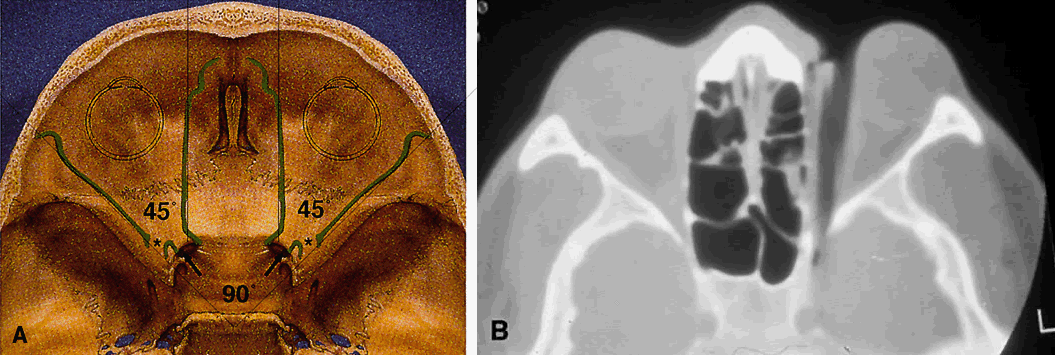

The lesser wing of the sphenoid bone is initially cartilaginous, but the greater wing and the rest of the orbital bones are membranous in nature and ossify and fuse between the 6th and 7th months of gestation. As the orbital bones develop, the eyes converge from an initial 180° relation to their final position of 68°, achieved in infancy. However, the orbital axis remains somewhat divergent at birth (115° between the lateral orbital wall and the skull axis) when compared with that of adults (45°) (Fig. 4).15

Fig. 11. Osteology. A. An axial view of the orbital roof demonstrates the parallel course of the medial orbital walls (green). The lateral orbital walls (green) lie at an angle of 90° from each other, or 45° from each medial wall. Remember that the superior orbital fissure, and not the medially placed optic canal, lies at the posterior aspect of the orbit. B. CT of a wooden foreign body within the orbit after trauma. Note that the tip has traveled through the superior orbital fissure and lies within the CS, not the optic canal. In this case, the greatest worry was not the patient's vision, but the possibility of lacerating injury of the carotid siphon, which was confirmed on subsequent arteriography (A modified from Zide BM, Jelks GW: Surgical Anatomy of the Orbit, p 9. New York, Raven Press, 1985. B courtesy John W. Shore, MD, Austin, TX)